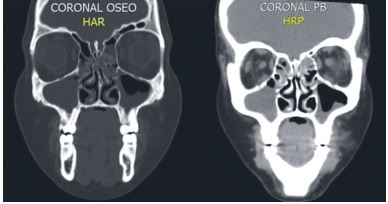

La tomografía axial (TAC) máxilo facial muestra velamiento de todas las cavidades perinasales con niveles hidro-aéreos de senos maxilares y senos esfenoidal (Figuras 2, 3 y 4), confirmando el diagnóstico imagenológico de PA.

Cuando el origen de la PA es dental, es necesario el control de la evolución del caso, mediante radiografías periapicales y TAC12; en este caso fue imprescindible la información dada por las imágenes del TAC para observar el velamiento de las cavidades de la región Máxilo facial y su adecuado diagnóstico.